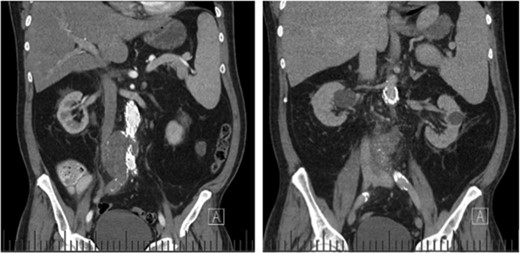

Computed tomography (CT) angiography revealed increased aortic size compared with a scan 1-month prior (5.4 cm compared with 5.0 cm) with diffuse peri-aortic inflammation. The findings implied an infected endograft (Figs 1 and 2).

Coronal CT images indicating enlarged aneurysm sac (left) and para-aortic fat stranding (right) representing periaortitis.